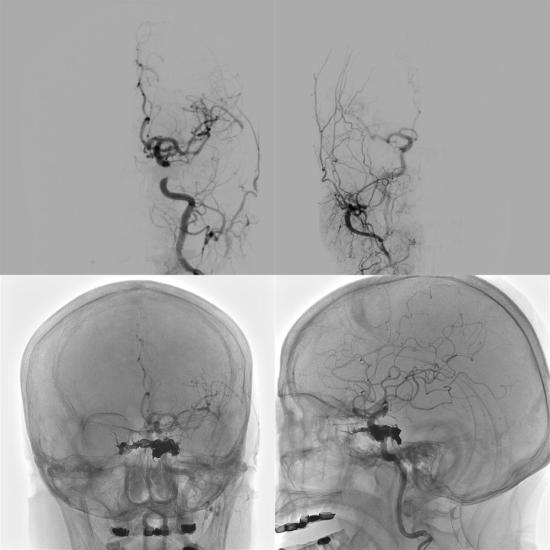

术后双侧颈动脉造影显示瘘口消失、血流正常